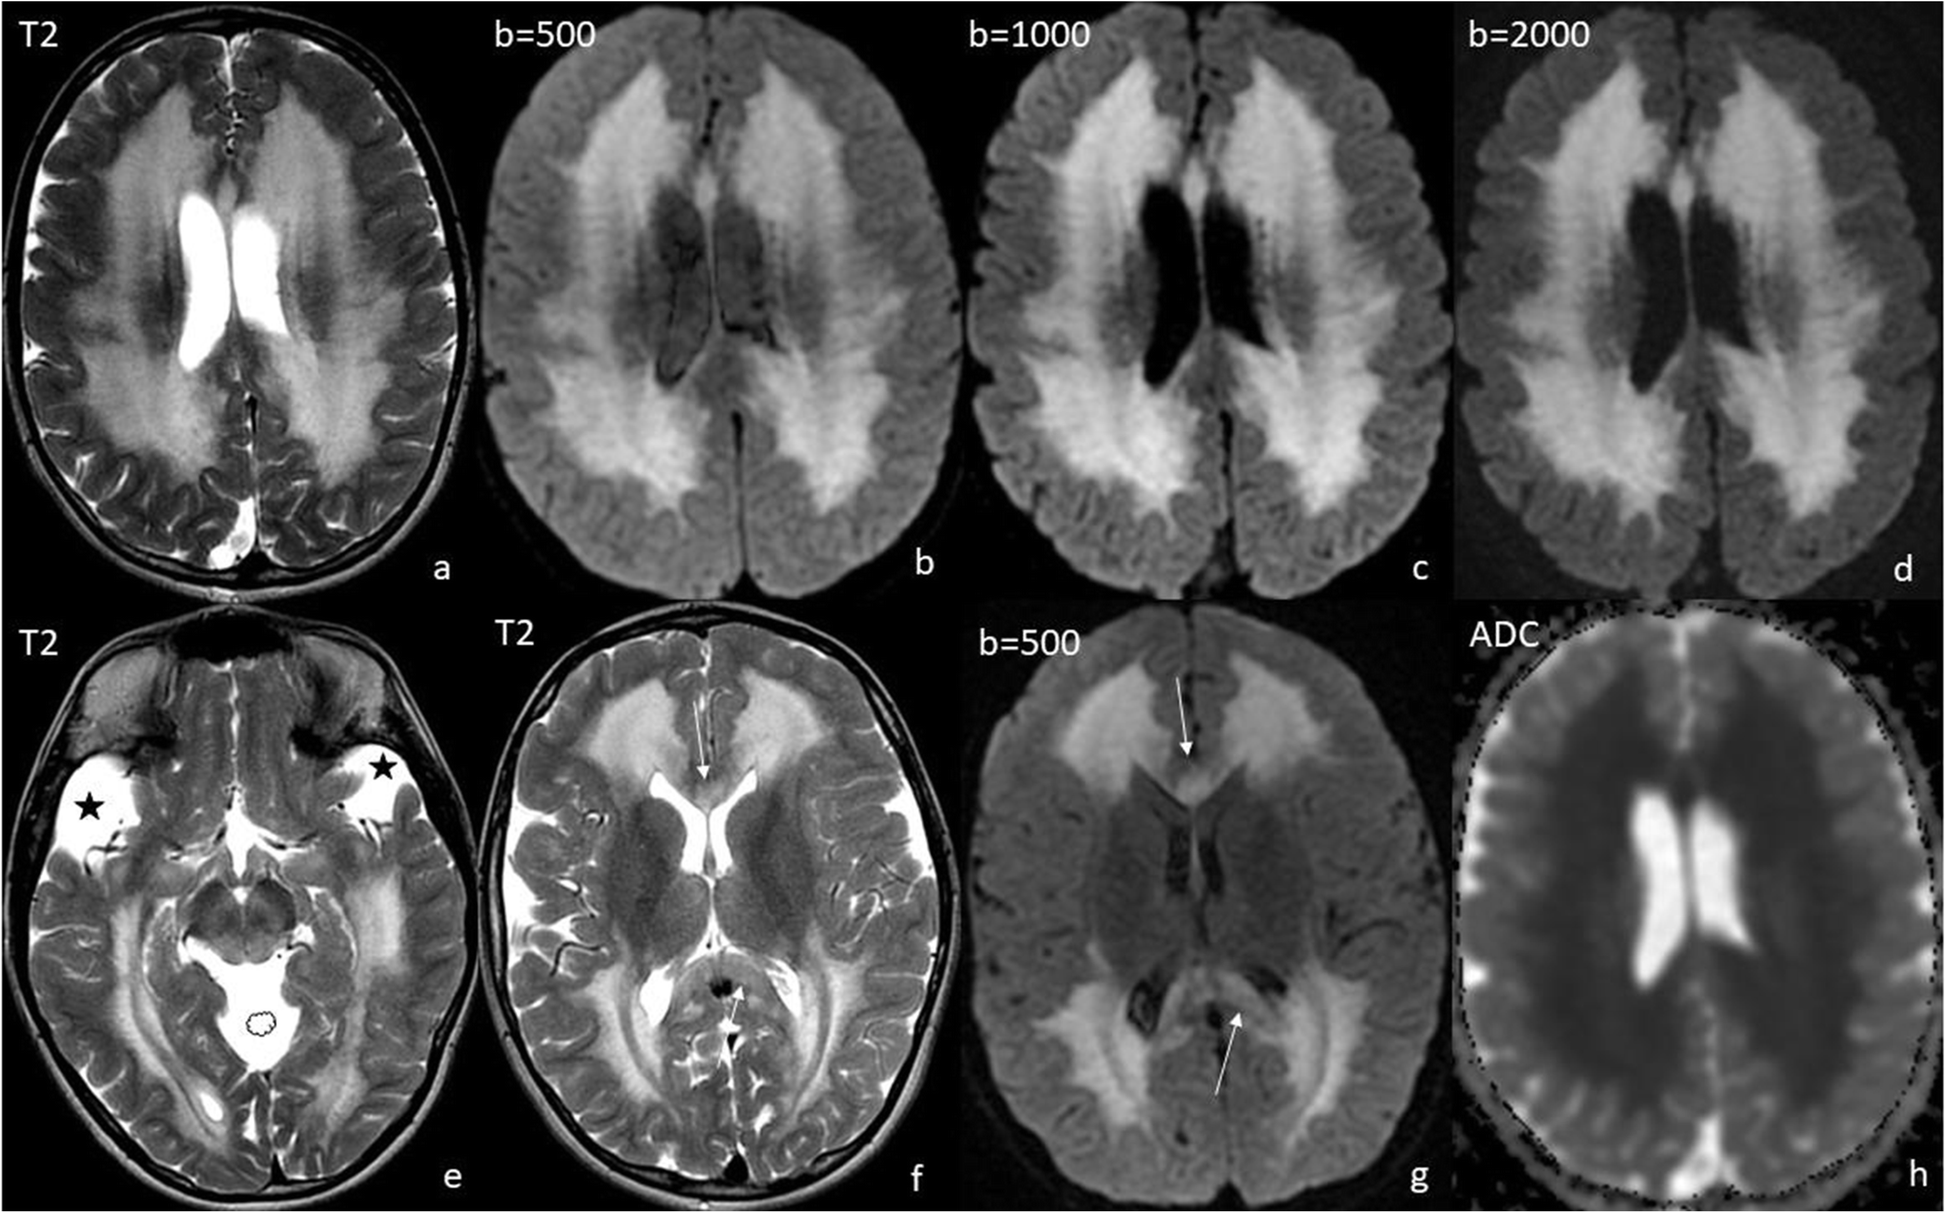

Fig. 3

Scan 3) at the age of 10 years. Diffuse symmetrical white matter involvement with tigroid pattern (a-g) and diffusion restriction (h). Note regression of subdural hygromas and of lesions in the pallidum as well as callosal involvement (f, g, arrows). Widened Sylvian fissures (asterisks) and mesencephalic cistern (cloud) as a constant feature of GA-1 (e)